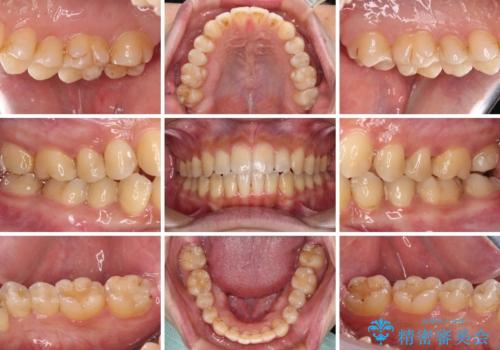

- 奥歯の目立つ銀歯と上下前歯の叢生と隙間を気にして来院された患者様です。

開咬の治療は、前歯を閉じるように動かすとともに、上下臼歯を圧下(骨内にめり込ませる)させることで進めて行きます。

インビザラインは臼歯の圧下を効果的に行えるため、インビザラインを用いて矯正治療を行うこととしました。

銀歯については、矯正治療により咬合関係を改善し、矯正治療後半に修復治療を行うこととしました。

修復治療後に細かい部分をインビザラインで再度仕上げるプランとしました。

銀歯のセラミック治療が1番の希望であったため、ここまで歯列がきれいに整うとは思ってなかったようで、大変喜んでいただけました。